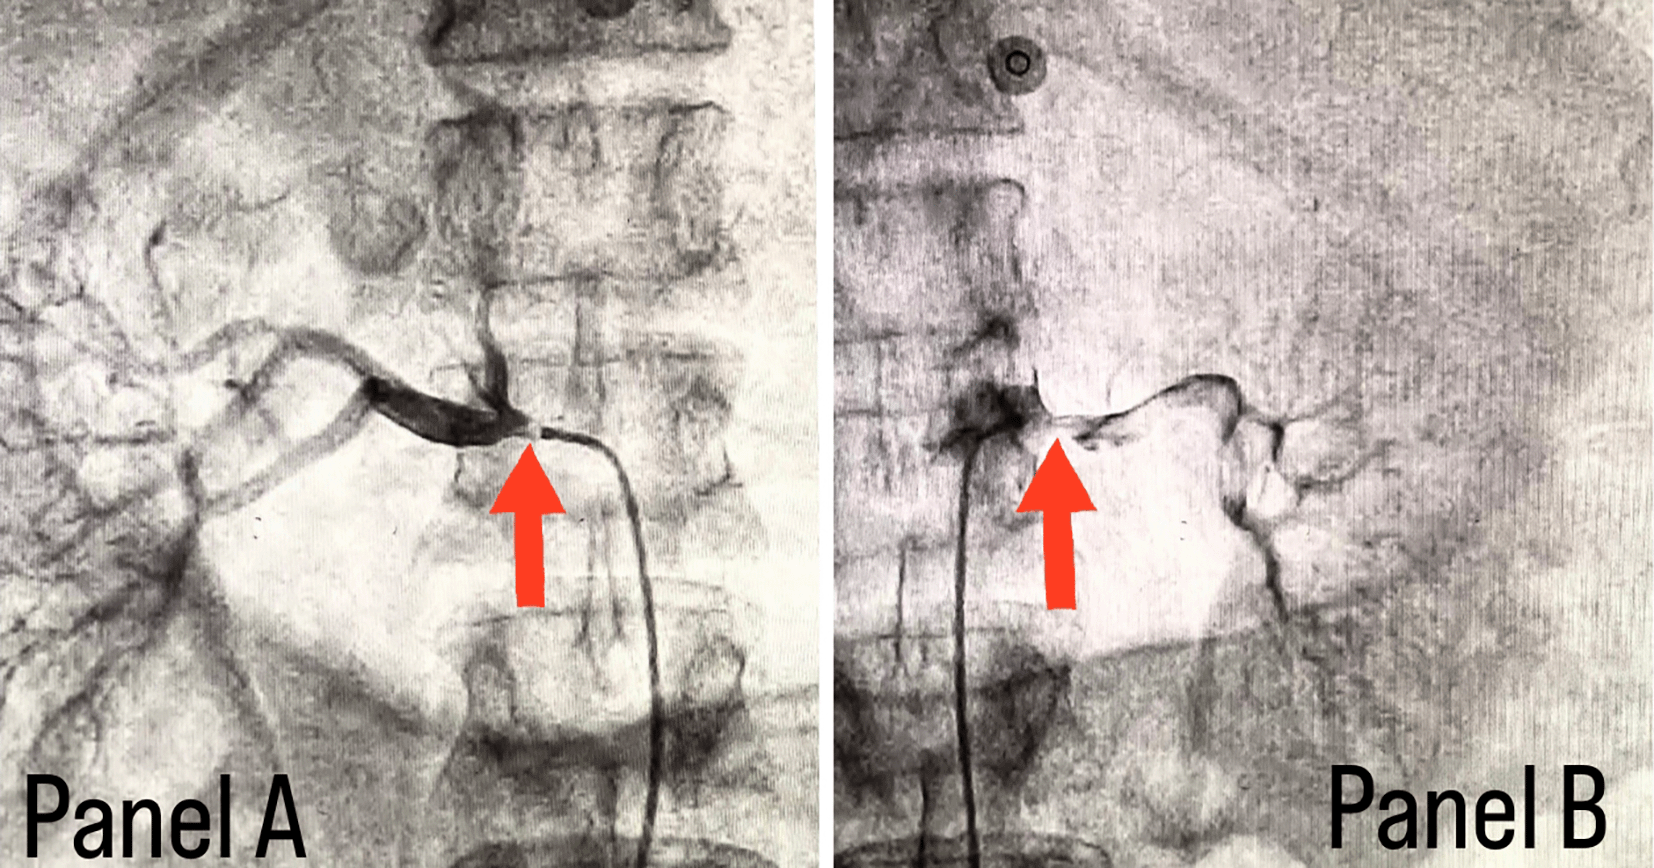

Coronary angiography was done and a triple vessel coronary artery disease was diagnosed as shown in Figure 1. A subclavian puncture was taken to look for a subclavian artery considering the claudication symptoms of the patient and peripheral vascular disease was diagnosed with bilateral subclavian artery stenosis as shown in Figure 2. Considering the severity of claudication pain in our case, bilateral renal and femoral arteries were also checked via aortic flush and bilateral renal artery ostial stenosis was seen, as shown in Figure 3, while the femoral arteries appeared normal bilaterally.